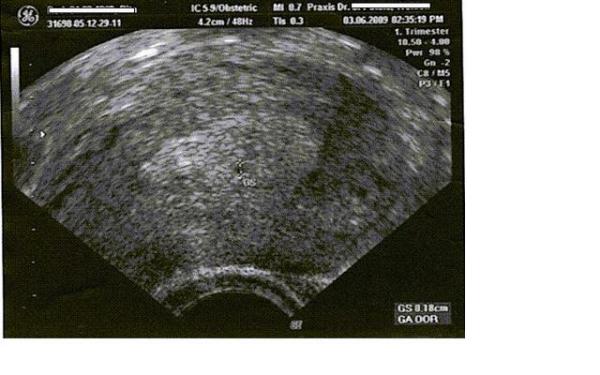

Aber wollte dich jetzt nicht kritisieren Pitry....bin ja auch kein Spezialist ![]() Anbei ein Ultraschallbild von mir aus der 6.SSW

Da ist de Fruchthöhle in der mitte zu sehen zwar nur ein ganz kleiner schwarzer Fleck,den der Arzt fast übersehen hätte aber dann doch noch entdeckt wurde....

Anbei ein Ultraschallbild von mir aus der 6.SSW

Da ist de Fruchthöhle in der mitte zu sehen zwar nur ein ganz kleiner schwarzer Fleck,den der Arzt fast übersehen hätte aber dann doch noch entdeckt wurde....